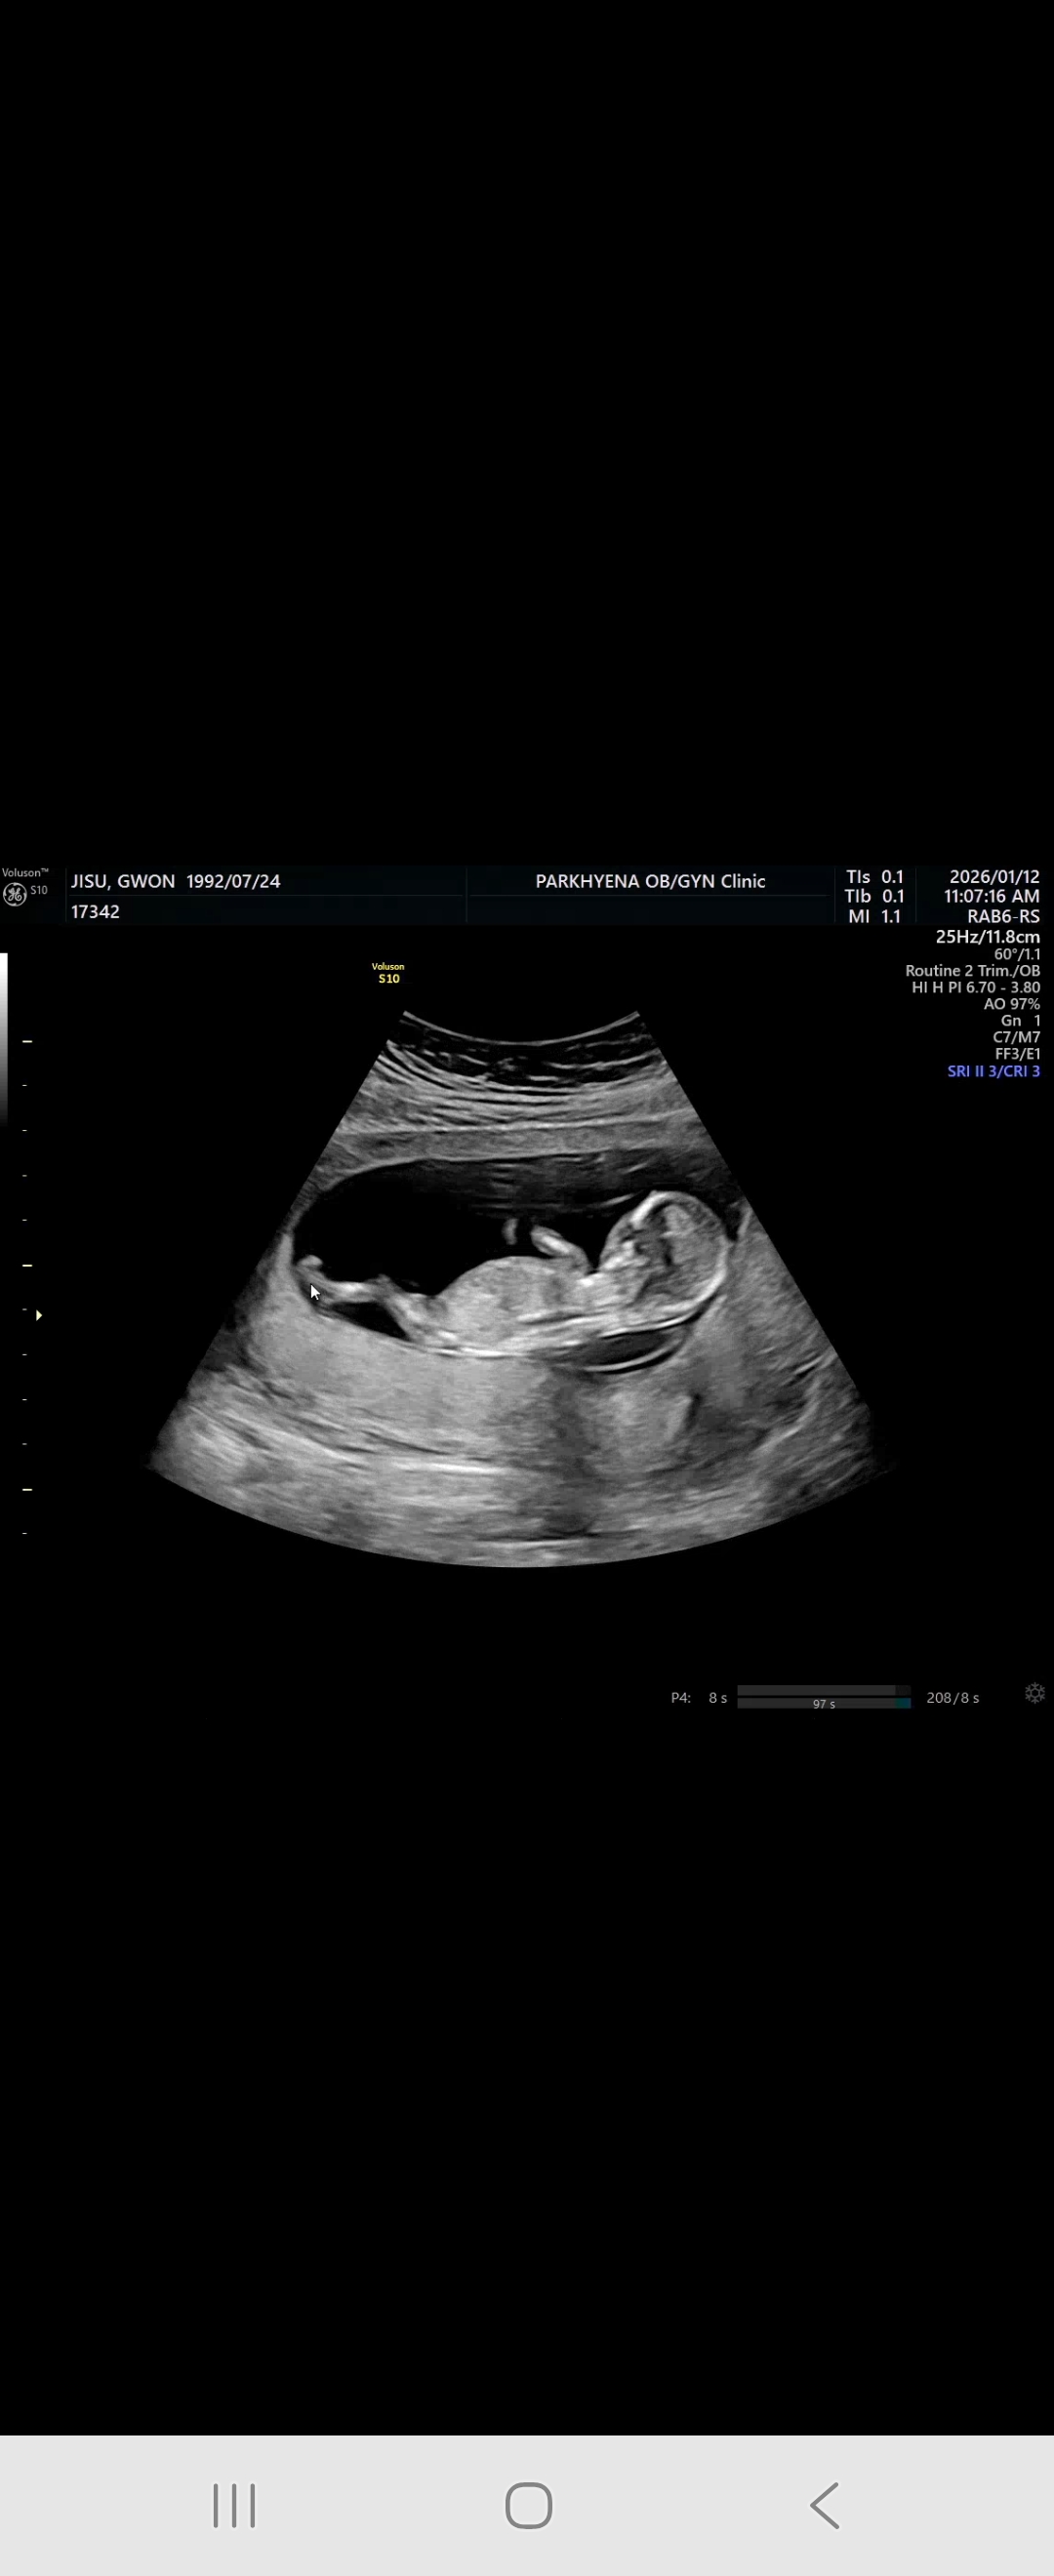

13주차 성별봐주세용

쌍둥이인데 얘만 잘보여서 한명만 올려봅니다ㅎㅎ 성별 넘넘 궁금해요ㅎㅎ